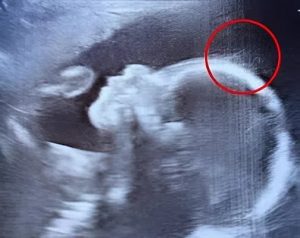

« Un instant… est-ce que ce serait… des cheveux ? » s’exclame-t-il, entre surprise et amusement. Un collègue rejoint la scène et observe, lançant avec humour que ce bébé semble déjà prêt pour le devant de la scène. Sur le moniteur, de délicates mèches ondulent avec grâce, offrant un spectacle aussi poétique qu’imprévu.

L’équipe rassure ensuite Émilie : il est tout à fait courant que la chevelure commence à se développer in utero. Ce qui sort de l’ordinaire, en revanche, c’est sa clarté et son abondance à ce stade de la grossesse, des détails rarement aussi nets lors d’une échographie.